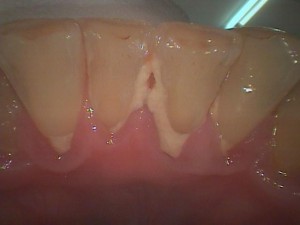

下顎の前歯です。

この場所は唾液腺の開口部があるので歯石が沈着しやすい場所です。

歯石が付着し歯肉が腫れている様子がわかります。歯肉も下がってきておりこのままにしておくと歯周病が進行します。歯周病は細菌感染が原因ですので、歯石(細菌の塊)除去と正しい歯磨きの方法を身につける事は非常に大切です。